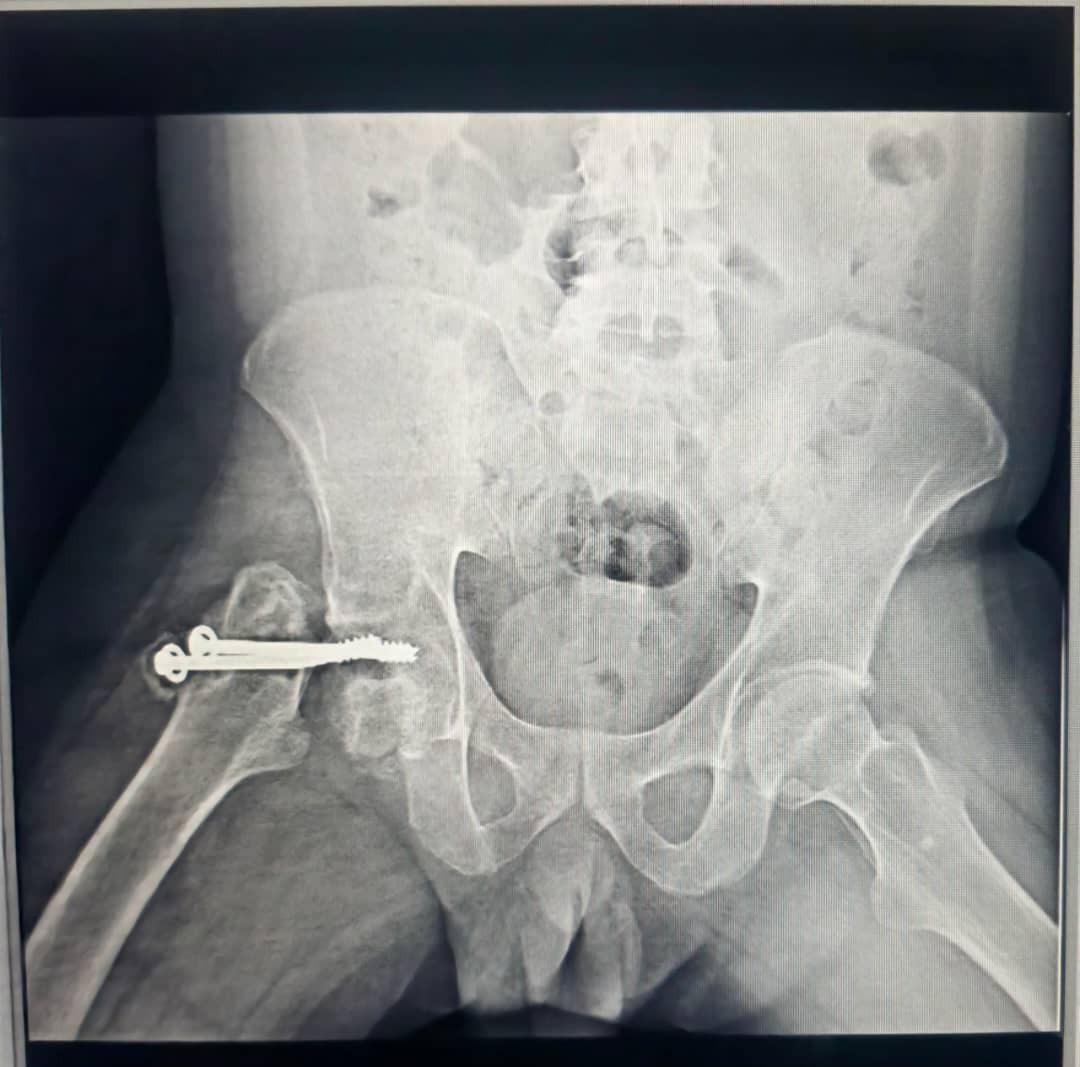

- En la cabeza del fémur, me colocaron dos tornillos porque, según el diagnóstico inicial, nunca volvería a caminar. Por eso decidieron no poner una prótesis en ese momento.

Poco a poco, con cada terapia, con cada pequeño avance, empecé a ver luz. Mis músculos recordaron lo que es moverse. Mi voluntad se hizo más fuerte que los pronósticos. Sin embargo, en medio de ese renacer, otro golpe: los tornillos de mi fémur nunca consolidaron. En lugar de ayudarme, me estaban dañando. Hoy necesito un soporte en la cadera para seguir con mis terapias; de lo contrario, no puedo avanzar.

- In my femoral head, they placed two screws because, according to the initial diagnosis, I would never walk again. That's why they decided not to implant a prosthesis at that time.

Little by little, with each therapy session, with each small advance, I began to see light. My muscles remembered what it was like to move. My will became stronger than the prognoses. However, in the midst of this rebirth, another blow: the screws in my femur never consolidated. Instead of helping me, they were damaging me. Today, I need a hip support device to continue with my therapies; otherwise, I cannot move forward.